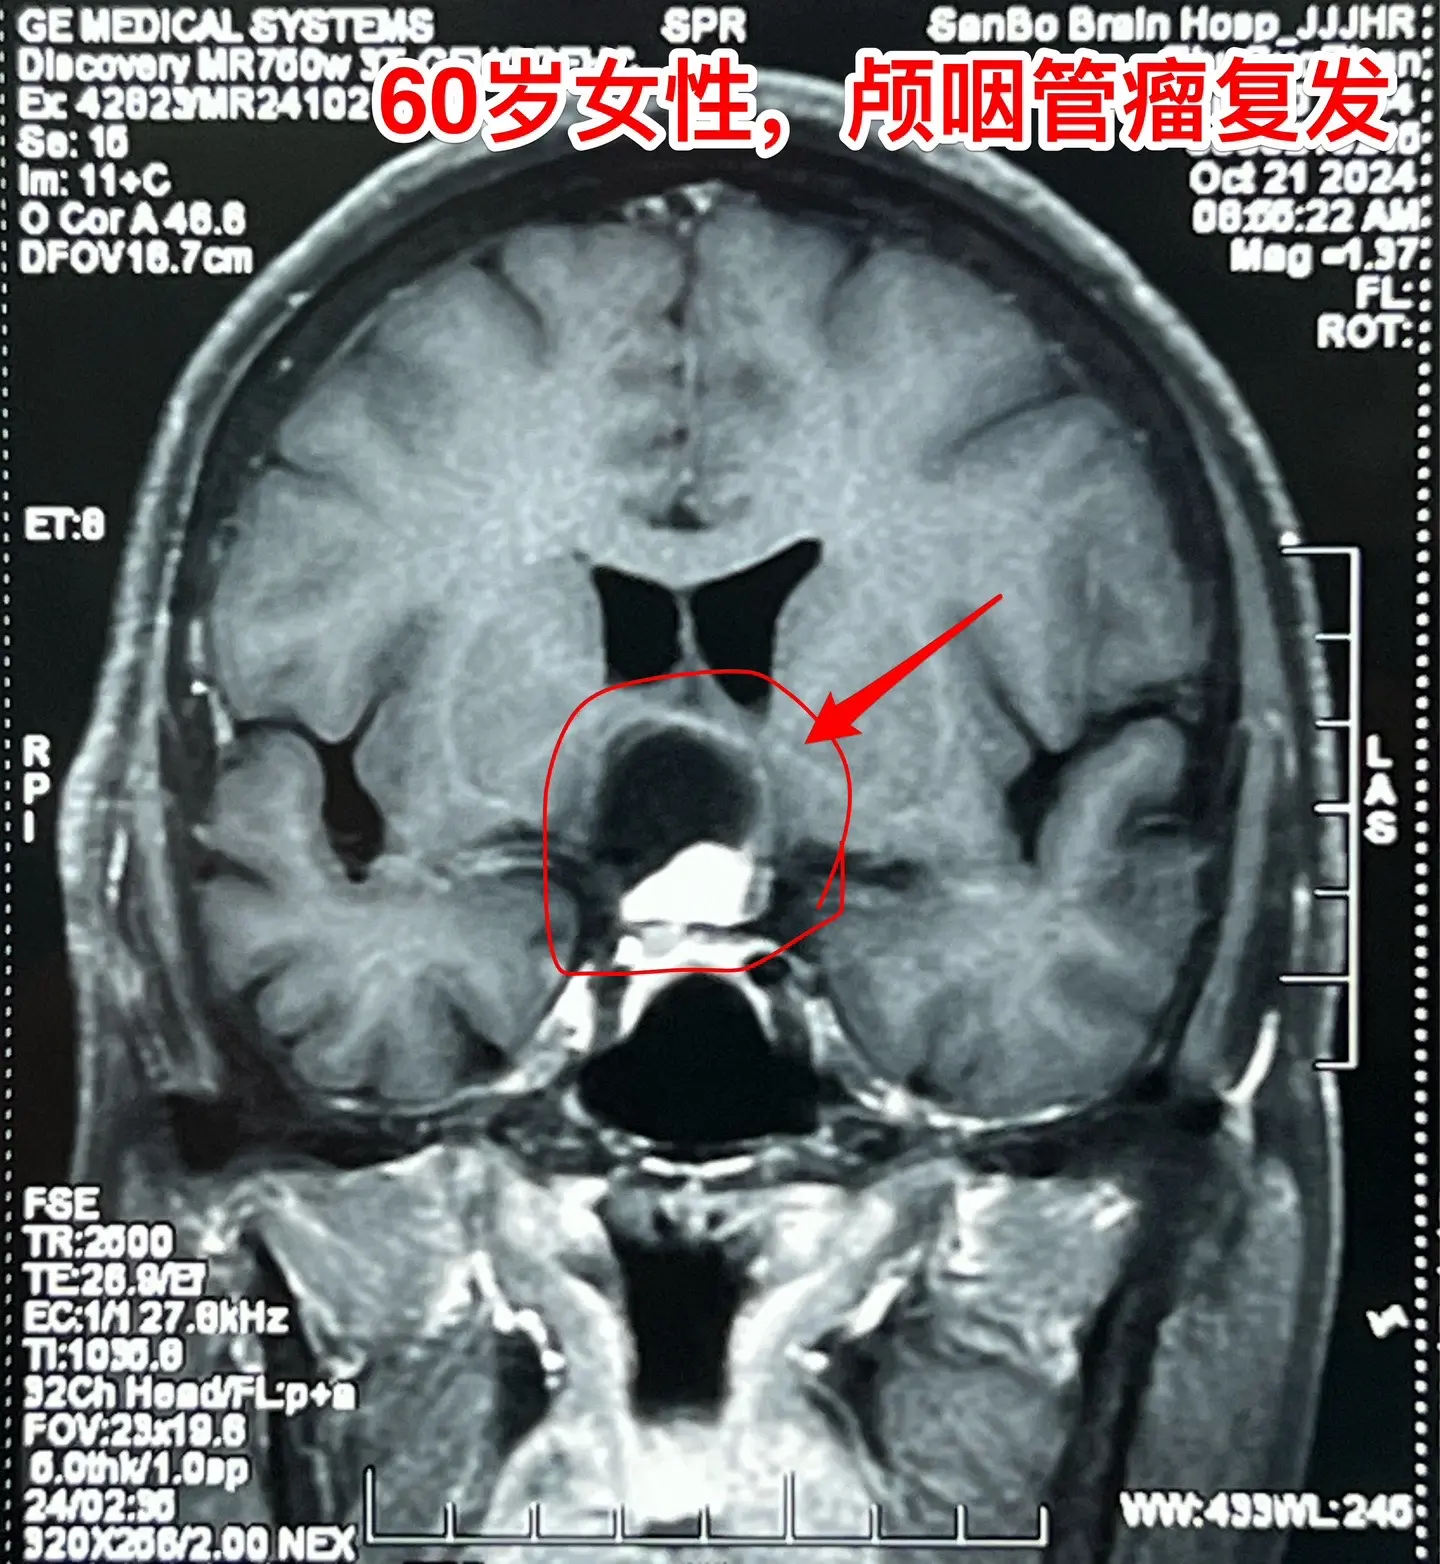

60岁连云港市的老人视力下降⬇️。老人自幼右眼受伤了,右眼视力属于无效视力,几十年内完全靠左眼来维持视力,能正常作事儿。 一年半前老人感到左眼视力下降了,到医院去检查,发现脑部长了颅咽管瘤。准备作手术治疗,在手术前作肺部CT的时候却意外发现肺部长了肿瘤,怀疑是肺癌,考虑到肺癌是恶性肿瘤,而颅咽管瘤是良性肿瘤,所以就先作肺癌切除术。肺癌手术后三个月又作了开颅手术,切除颅咽管瘤,手术后左眼视力有好转。 一个人居然同时长了两种肿瘤!真是祸不单行! 今年九月份患者左眼视力又出现下降,快失明了。在当地医院复查磁共振显示肿瘤复发了,十月份来我科住院。10月31日作了开颅手术,将颅咽管瘤切除了。手术后老人说视力有好转。